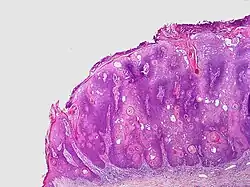

Visual diagnosis is made by the "stuck on" appearance, horny pearls or cysts embedded in the structure. Darkly pigmented lesions can be challenging to distinguish from nodular melanomas.[10] Furthermore, thin seborrheic keratoses on facial skin can be very difficult to differentiate from lentigo maligna even with dermatoscopy. Clinically, epidermal nevi are similar to seborrheic keratoses in appearance. Epidermal nevi are usually present at or near birth. Condylomas and warts can clinically resemble seborrheic keratoses, and dermatoscopy can be helpful to differentiate them. On the penis and genital skin, condylomas and seborrheic keratoses can be difficult to differentiate, even on biopsy.

A study examining over 4,000 biopsied skin lesions identified clinically as seborrheic keratoses showed 3.1% were malignancies. Two-thirds of those were squamous cell carcinoma.[11] To date, the gold standard in the diagnosis of seborrheic keratosis is represented by the histolopathologic analysis of a skin biopsy.[12]